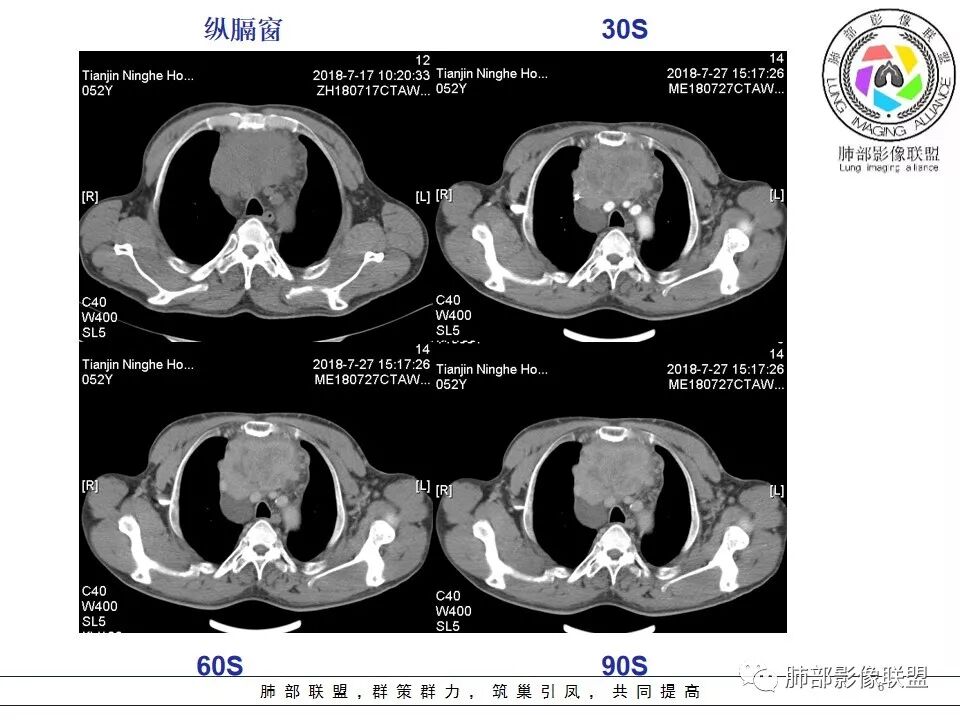

我们分析一下影像.

较大,内有囊变、钙化。

南边:边界大部分清楚,有些地方毛糙。

南边:强化就不用说了

大肿块,边缘不清,伴随肿大淋巴结,上腔静脉受侵犯——恶性

侵袭性胸腺瘤?胸腺癌?老年,钙化、肿大淋巴结,边缘侵犯、累及心包、侵犯上腔静脉——支持

患者前纵隔囊实性肿块,常规疾病普考虑胸腺瘤、胸腺癌、生殖细胞肿瘤、淋巴瘤和神经内分泌肿瘤,其中神经内分泌肿瘤中最常见的是类癌,患者的年龄不支持生殖细胞瘤,具体分析如下:

1.  病灶内实质性钙化,提示AB型以上胸腺瘤、胸腺癌或类癌,其中微钙化往往提示高危型胸腺瘤跟胸腺癌、类癌,同时也排除了淋巴瘤(淋巴瘤不会有钙化);

2.  病灶呈分叶蔓延倾向,其内大片状囊变坏死,周围脂肪间隙模糊,提示高危型胸腺瘤或胸腺癌,但是类癌周围脂肪间隙往往很清晰;

3.  胸膜、心包侵犯,多提示高危型胸腺瘤中的B3型胸腺瘤、胸腺癌、类癌

4.  纵隔淋巴结肿大及纵隔大血管(上腔静脉)受侵犯,提示胸腺癌或类癌。